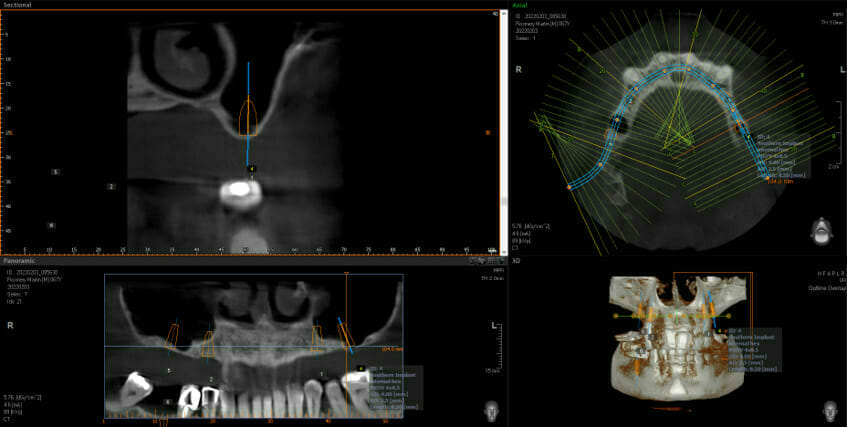

This shows big black areas where the sinuses are and shows that there is not enough bone to put the implants in (shown in orange). You don’t have to be an implantologist to see how much bone we have after the grafting. Now we can go ahead and place 2 implants each side at the back and this allows the addition of 3 new back teeth each side (using implant bridges means we still only need 4 implants, not 6, keeping surgical complication and costs down)

After Sinus Bone Grafts with 2 out of the 4 implants in place